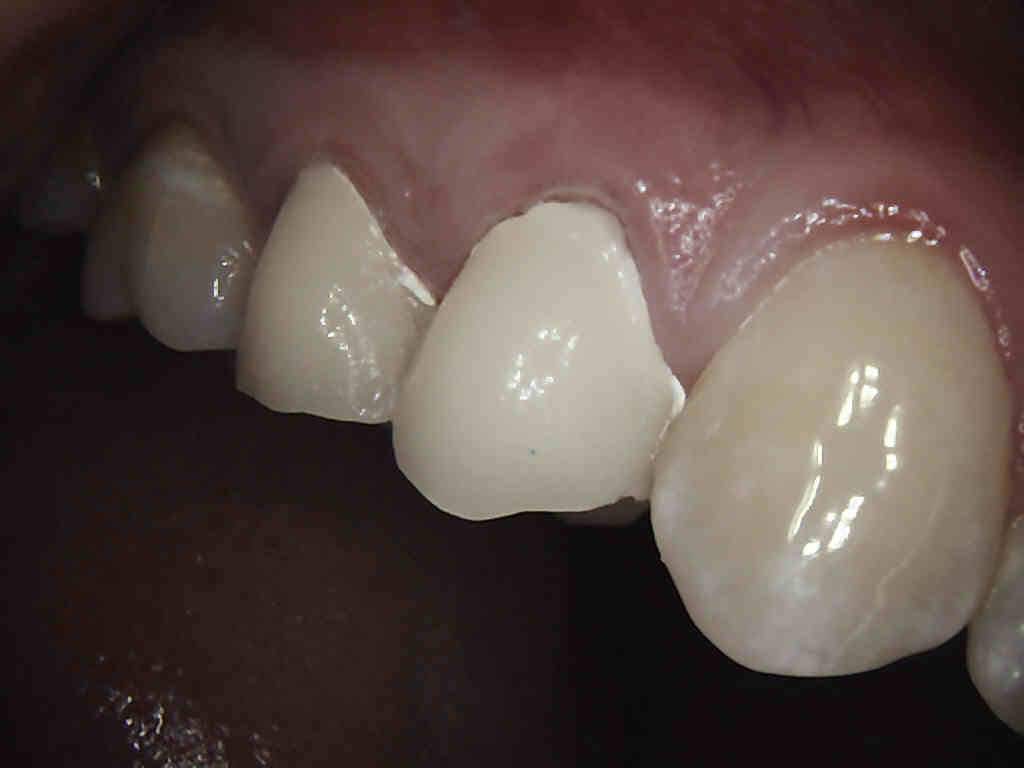

Porcelain crowns and restorations made in one appointment.

We make it a priority to incorporate the latest in dental technology in everything we do at our practice. ...